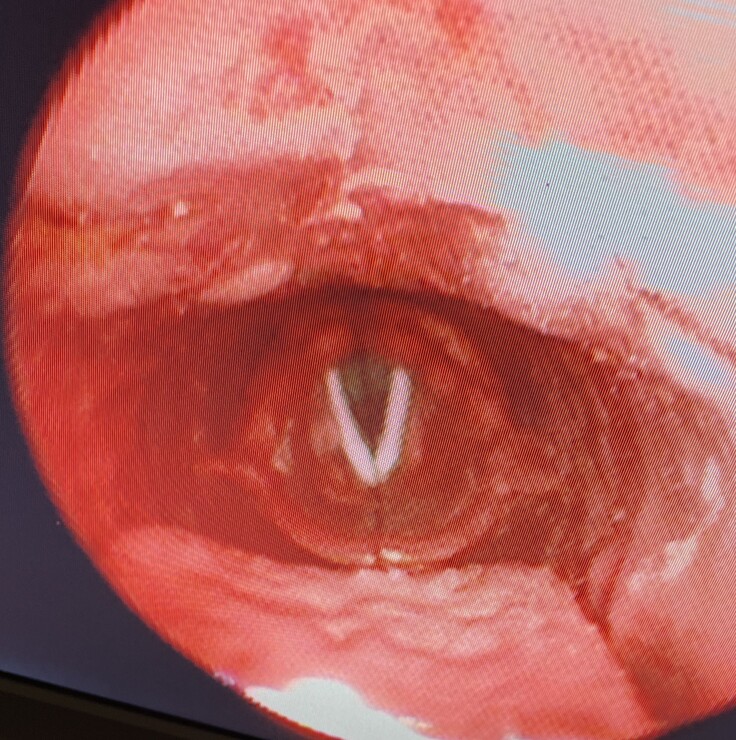

喉頭の形態

喉頭の形態は、歯科医師の自分が持っていた内視鏡で観ていたイメージと実際の形態は若干、違っていました。

*添付画像は、マネキンの現在の咽喉頭画像です。

画質が粗くてすみません

お気づきの点がございましたら、ご教示ください